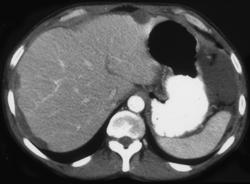

Carcinomatosis Due to Gastric Adenocarcinoma